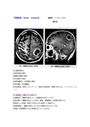

*正常神経系細胞から発生する腫瘍 ≪神経膠腫≫ ・疾患概念 脳腫瘍の40%を占める。膠細胞と髄芽細胞から発生する。 ... 乏突起膠腫は成人に発生するまれな腫瘍、脳室上衣腫は50%が、髄芽腫は全例が小児期に発生し、両者合わせて全脳...

原発性脳腫瘍と転移性脳腫瘍について。 原発性脳腫瘍とは、頭蓋内の組織に単体として発生した腫瘍のことである。原発性脳腫瘍が脳から他臓器に転移するこ